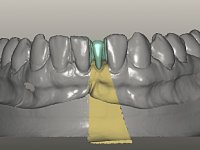

The deciduous tooth was extracted and a provisional resin crown with two small wings was bonded to the lingual surfaces of adjacent teeth. Two months later, the provisional crown was removed and the proximal walls were slightly prepared in order to parallelize the proximal walls and slight augment the mesio-distal space. After this minimal invasive dentistry, a dental impression was done with addition silicones in a one-stage technique. A provisional resin crown with an orthodontic wire on the buccal surface was then bonded to the adjacent teeth with resin, avoiding changing the prepared proximal and lingual surfaces.

In the dental lab, a Maryland bridge with a zirconia framework veneered with a feldspathic ceramic was built. The wings internal surface also had a very thin coating of a zirconia adhesive to allow its bonding to the abutments enamel. This Maryland bridge tried to join the mechanical strength of the framework, to the bonding of the ceramic to the enamel, and to the aesthetics’ of the zirconia’s veneering with a feldspathic ceramic.

Then, this Maryland bridge was bonded to the abutments.